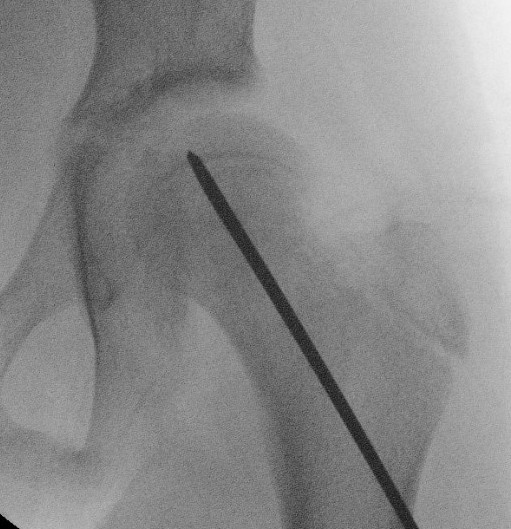

Intra-capsular / Subcapital

Types

Dunn

- trapezoid osteotomy

Fish

- cuneiform